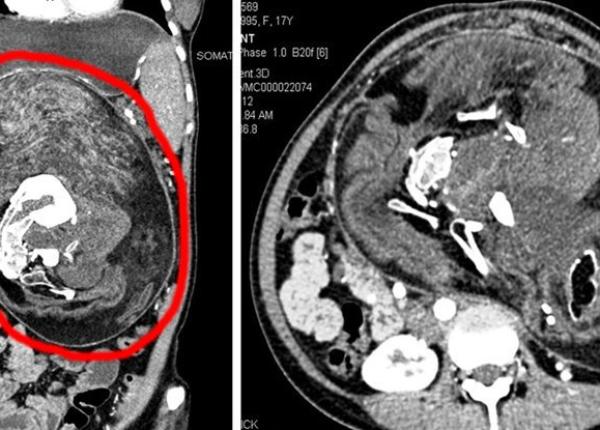

Caz medical rar: tânăra care a trăit 17 ani, având în abdomen resturi din fratele parazitar

O tânără din India a purtat în abdomen până la 17 ani resturi din fratele ei geamăn parazitar, din viața intrauterină. Cazul este extrem de rar.